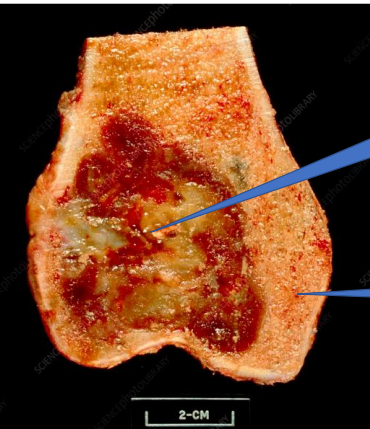

1- Bone Tumor

2- Normal bone